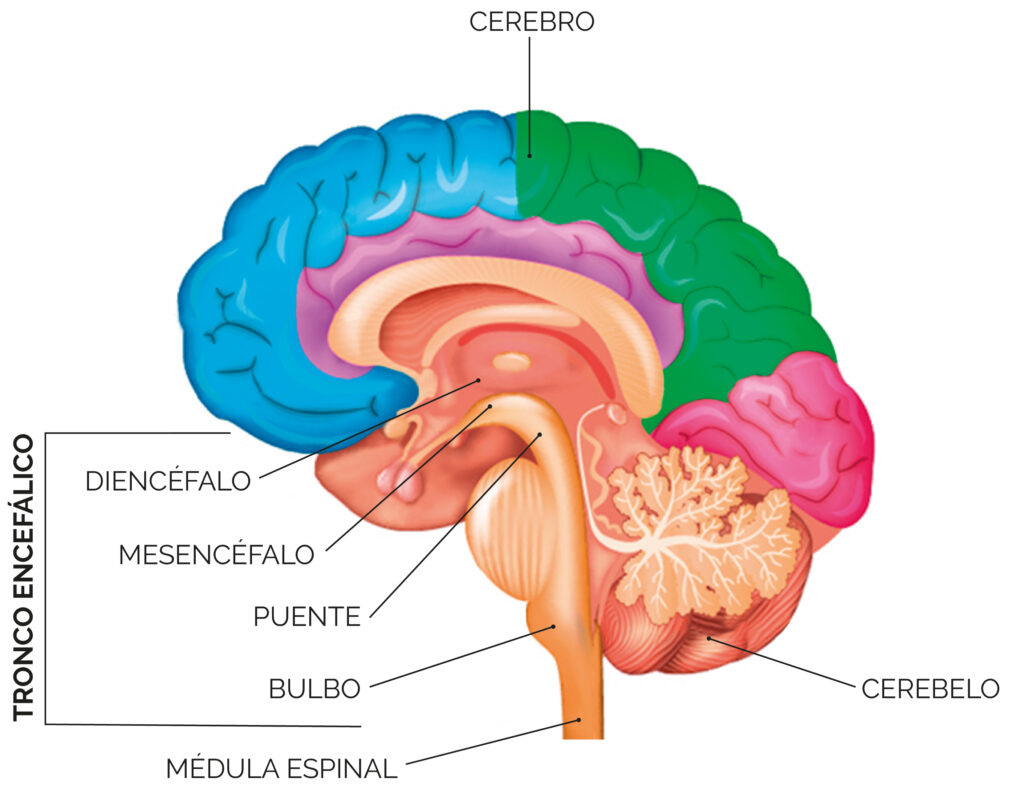

El encéfalo se divide en dos porciones por la tienda del cerebelo:

- Infratentorial: con la médula oblonga, el puente, el cerebelo y los pedúnculos cerebelosos.

- Supratentorial: con los pedúnculos cerebrales y el cerebro propiamente dicho.

La región que reúne las porciones infratentorial y supratentorial, recibe el nombre de:

👉istmo del encéfalo

El istmo del encéfalo, corresponde a:

🔹los pedúnculos cerebrales.

🔹los pedúnculos cerebelosos superiores.

El tronco encefálico está formado de caudal a craneal, por:

🔹la médula oblonga

🔹el puente

🔹el mesencéfalo

El encéfalo desde el punto de vista de su desarrollo embriológico se puede dividir en:

🔹Encéfalo posterior o rombencéfalo

🔹Encéfalo medio o mesencéfalo

🔹Encéfalo anterior o prosencéfalo

Encéfalo posterior o rombencéfalo, proviene de la vesícula posterior, dando origen a:

🔹la médula oblonga.

🔹el puente.

🔹el cerebelo.

Encéfalo medio o mesencéfalo, proveniente de la vesícula media y comprende:

🔹los colículos superior e inferior

🔹los pedúnculos cerebrales con el acueducto del mesencéfalo.

Encéfalo anterior o prosencéfalo, formado de la vesícula anterior se divide a su vez en:

🔹diencéfalo (tálamo, hipotálamo, región subtalámica, epitálamo y metatálamo).

🔹telencéfalo (corteza cerebral, cuerpo estriado y sustancia blanca).